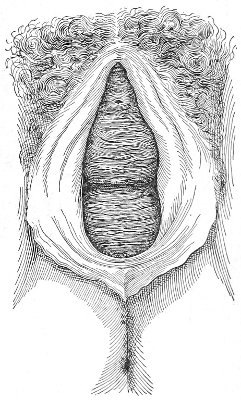

The Sims speculum enables us to make the most thorough inspection of the vagina, the vaginal vault, and the vaginal cervix. The Sims speculum is merely a hook or retractor for the perineum, and may be introduced with the woman in the dorsal position, the Sims position, or the genu-pectoral position. If the Sims speculum is introduced in the dorso-sacral position, it is necessary to hold forward the anterior vaginal wall in order to obtain a view of the cervix.

Fig. 10.—The Sims position.

The Sims position, which is also called the latero-abdominal position, is shown in Fig. 10. The woman is placed on the bed or table upon her left side. The side of the face is upon the pillow; the left arm is behind the back, so that the left breast rests upon the table. The thighs are flexed upon the abdomen at an angle of about 90° to the trunk. The right thigh is more flexed than the left, so that the right knee may touch the table above the left knee. The legs are flexed on the thighs. In this position there is a tendency for the intestines, following the force of gravity, to fall from the pelvis, 32 and for the uterus and other pelvic viscera to be drawn up. When the perineum is retracted with the blade of the Sims speculum, air will enter the vagina and the vaginal slit will become distended (Fig. 11). To facilitate inspection of the cervix it is usually necessary also to push forward the anterior abdominal wall by some kind of depressor, such as the one shown in Fig. 8.

Fig. 11.—The cervix uteri exposed with the Sims speculum.